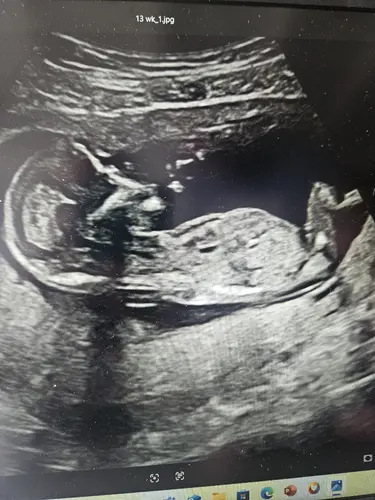

Ik ben heel benieuwd wat jullie hiervan kunnen maken! Het maakt me niet uit wat het wordt, maar ik ben zo enorm nieuwsgierig! Deze echo is gemaakt bij 13 weken en 0 dagen. Hopelijk kunnen jullie er wat theorieën op loslaten! ☺️

Als ik goed naar dit echo-beeld kijk, lijkt de nub wat meer horizontaal/parallel aan de ruggengraat te liggen, niet sterk omhoog gericht. Volgens de NUB-theorie zou dat meer richting meisje wijze